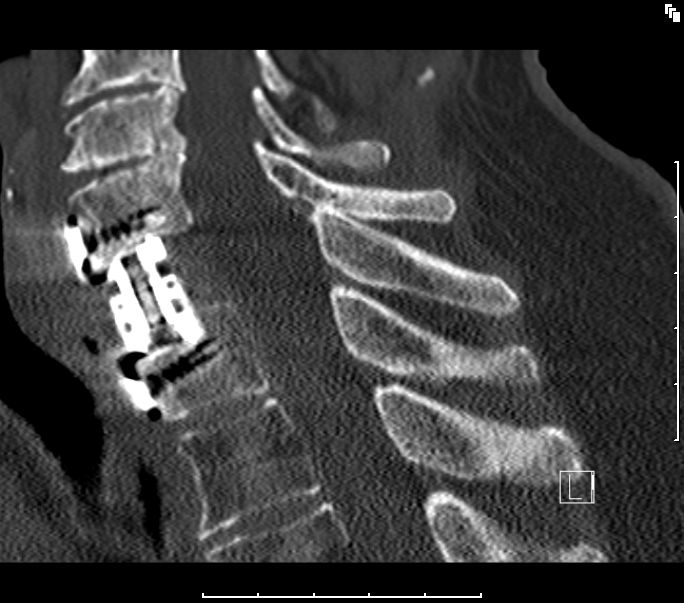

bildgebende Diagnostik